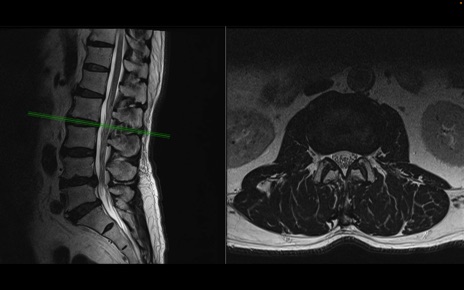

【整形】TIPS症例2 腰椎MRI 横断像と矢状断像

【症例】70歳代男性

【主訴】左下肢痛

【現病歴】2週間前くらいから腰痛、左下肢痛あり。左臀部から大腿、下腿外側のしびれが常時ある。歩行とともに同部位の痛みあり。

【身体所見】Lasegue70-/60+、Bragard-/±、PTR ±/±、ATR -/-、IP 5/5、TA 5/4、TS 5/5、EHL 右第1足趾なし/3、FHL 5/5、hypersthesia(-)、足背動脈触知良好

異常所見と診断は?